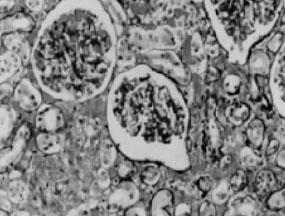

肾动脉狭窄最常见于肾动脉开口处或近端1/3血管,非开口处血管病变仅占15%~29%,肾动脉主干远端仅占5%。动脉粥样硬化引起的肾动脉狭窄主要累及大中动脉,动脉内膜粥样斑块,溃疡或血栓形成,多为双侧病变(见图5—1,图5—2)。

图5—1 肾动脉粥样硬化,管腔狭窄